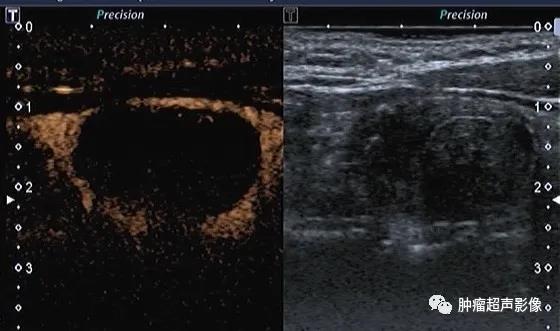

本次讲解的甲状腺皱缩结节容易被误诊为乳头状癌。 甲状腺皱缩结节:甲状腺囊性结节或囊实性结节中囊液吸收,胶质减少、自发性塌陷、皱缩...